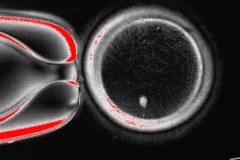

This undated image provided by the Mitalipov Laboratory at Oregon Health & Science University shows a a microscope image of a human egg that contains a nucleus taken from a skin cell. (Mitalipov Laboratory via AP)   (Associated Press)

The OHSU team removed the nucleus from a human egg cell and replaced it with the nucleus from a human skin cell. But a skin cell contains two sets of chromosomes, and eggs and sperm are supposed to each contain only one set that combine during fertilization. The researchers therefore induced the egg-like cells to discard extra chromosomes, injected donated sperm and jumpstarted post-fertilization development.